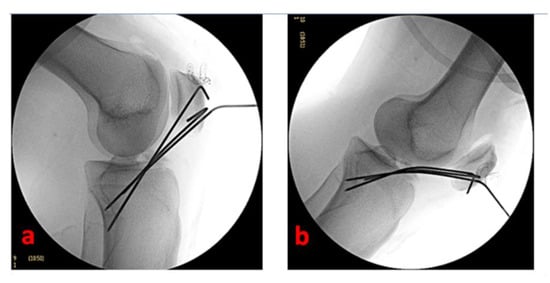

Standard anteromedial, anterolateral, and superolateral arthroscopic portals allow for full access to knee visualization, favoring a complete and direct visualization of the tibial eminence avulsion. We prefer to avoid the trans-tendinous Gillquist central portal [34], but we systematically use a modified Patel’s medial mid-patellar (superomedial) portal [35] or more patient-specific accessory ones if necessary to address associated intraarticular lesions. A thorough hematoma and blood clot washing and a selective Hoffa’s pat debridement are performed to achieve clear visualization of the joint. Care should be taken to avoid the complete removal of Hoffa’s pad to limit the post-operative knee stiffness. The eventual interposition of the intermeniscal ligament or the entrapment of the anterior horn of the medial or lateral meniscus in the fracture site can be easily managed by extracting them with an arthroscopic probe or a pick. The concomitant intraarticular lesions are arthroscopically addressed and managed according to the consolidated surgical modalities. We perform the debridement of the inflammatory tissue in the fracture site with a full-radius shaver blade and the reduction in the fracture by using a less-invasive bone impactor. With the knee flexed to 90°, the fracture fragments are then synthesized (under fluoroscopic control) with three thin Kirschner wires (maximum diameter: 2 mm) inserted in a proximal–distal direction in a cross-shaped geometry and guided by 2.4 mm cannulated aimers (Figure 3).

Figure 3.

Arthroscopic view of tibial spine avulsion management of the left knee of a 16-year-old female patient—(a): light fracture site debridement is necessary to grant adequate visualization; (b): the reduction of the fracture is facilitated by using a less-invasive bone impactor; (c): a cannulated aimer is a useful tool to drive the Kirschner wires positioning; (d): the osteosynthesis is performed and completed by positioning three thin Kirschner wires in a cross-shaped geometry.

Cannulated aimers are also useful in performing a moderate compression of the fracture fragments while inserting the Kirschner wires. Two K wires are inserted through the superolateral portal to reduce the tibial intercondylar eminence (and mimic the orientation and the force lines of ACL fibers), and 1 K wire is inserted through the superomedial portal [35]. According to our experience, the Kirschner wires should ideally reach the opposite tibial cortical surface to strengthen the osteosynthesis mechanism. Caution must be taken to prevent iatrogenic damage to the external popliteal sciatic nerve; for this reason, we suggest pre-determining and equalizing the length of the Kirschner wires after the careful positioning of the first one under fluoroscopic control.

Under arthroscopic and fluoroscopic visualization, we completely extend the knee to confirm the effectiveness of reduction and stability. The Kirschner wires are externally cut (by maintaining a 2–3 cm straight external portion—essential for the subsequent removal) and curved (Figure 4).